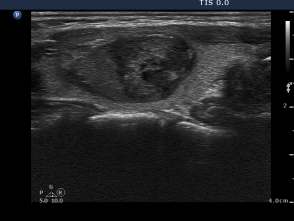

Second session of sclerotherapy (third row of images):

The second session was performed nine days after the previous one. The nodule became a bit larger. Now we could aspirated 15 mL brown fluid form the nodule, therafter we injected 5 mL ethanol.